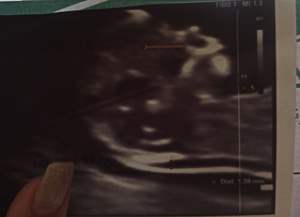

jggdewopyr مدیر استارتر عضویت: 1401/09/05 تعداد پست: 1475 پسر.دکتر احتمال نداد؟ از کجا میفهمین؟ دکتر اول گف پسر بعدا گفت دختر

آنشرلی_باموهای_مشکی عضویت: 1397/09/29 تعداد پست: 11406 از کجا میفهمین؟ دکتر اول گف پسر بعدا گفت دختر جمجمه https://harfeto.timefriend.net/17567192787641🍁

elijj عضویت: 1402/03/25 تعداد پست: 3904 عزیزم از کجا میفهمین پسر دختری رو از جمجمش الان یه عکس میذارم ببین پسر این شکلیه مامان یه دخمل گوگولی

آنشرلی_باموهای_مشکی عضویت: 1397/09/29 تعداد پست: 11406 الان بنظرت پسره؟ ان شاءالله سالم باشه به نظر من پسر https://harfeto.timefriend.net/17567192787641🍁